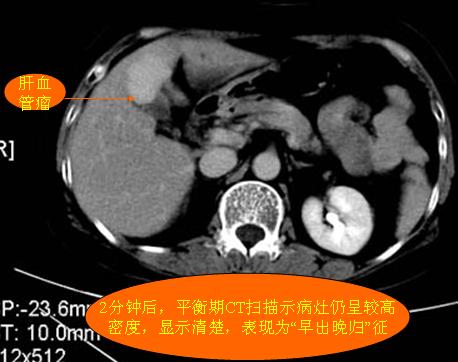

腹部ct解剖与基本病变